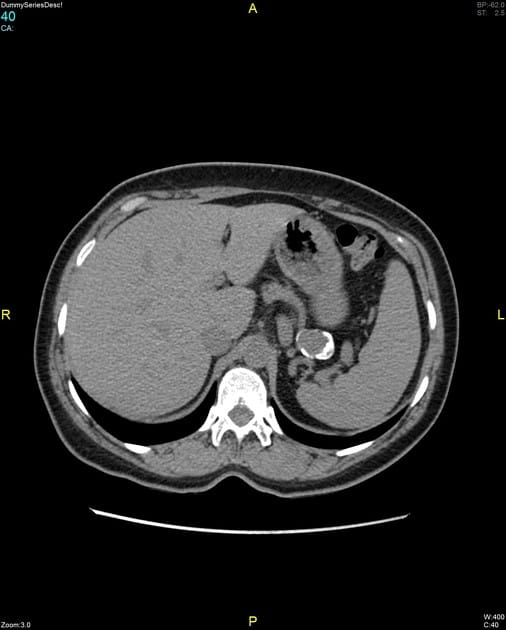

Phình ĐM lách (Sao chép) - BỆNH TIM MẠCH